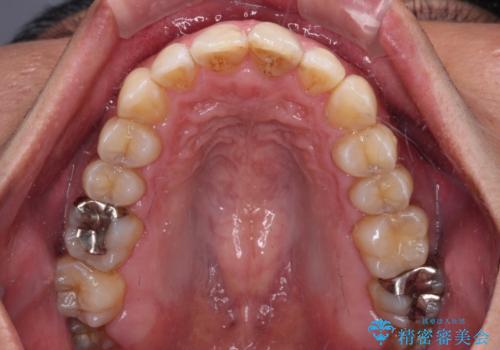

- 前歯のデコボコを気にして来院された患者様です。

下顎前歯のデコボコが特に強く、治療を早く終えることを考えるとワイヤー装置がお勧めですが、ワイヤー装置の異物感は避けたいのでインビザラインを希望されていました。

インビザラインで治療を行うか、ワイヤーで治療を行うかずっと悩んでいらっしゃいましたが、早く終わらせることを優先してワイヤー装置にて治療を行うこととしました。

下顎にワイヤー装置を装着し、暫くしたところでやはりインビザラインにて矯正治療をしたいとのことで、インビザラインに切り替えました。

短い期間でしたがワイヤー装置を使用したことでデコボコが解消されたため、インビザラインの比較的短い期間で矯正治療を行うことができました。